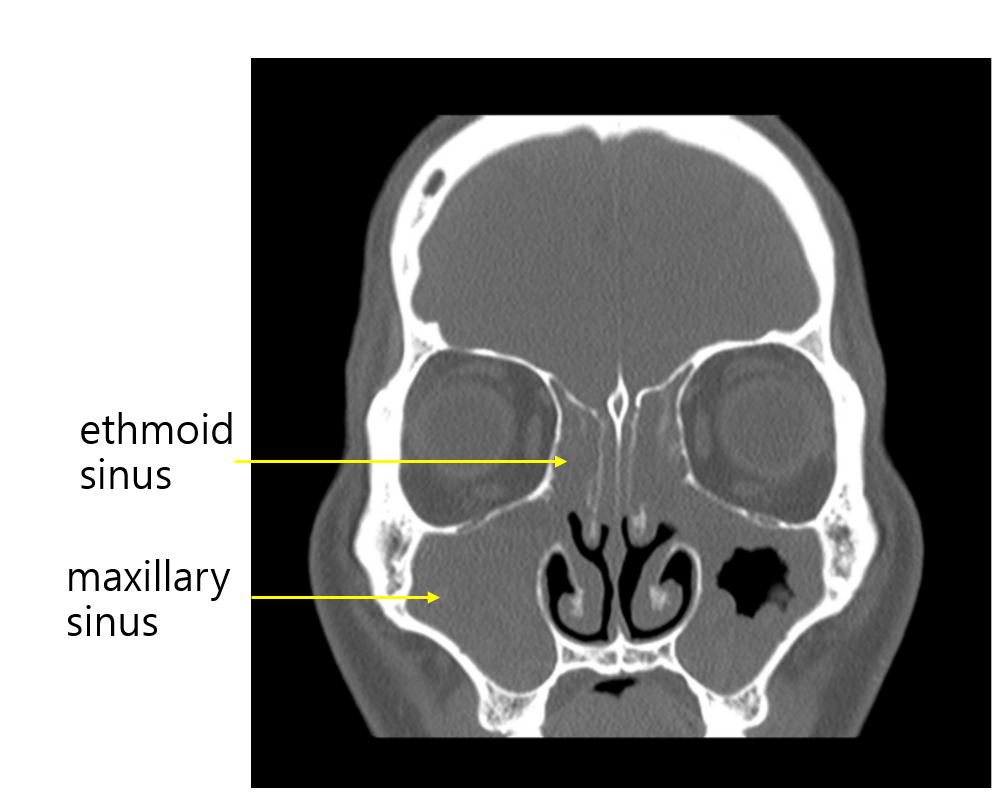

Img | Brain CT : Bilateral maxillary sinusitis |

• 만성적인 농성 비루, 기침과 brain CT에서 maxillary sinuses, ethmoid sinuses에 soft tissue density로 가득 차있는 소견을 통해 만성 부비동염(chronic sinusitis)로 진단 가능하다.

• 비중격교정술: 비중격만곡증(septal deviation)으로 인한 비강폐쇄에서 필요한 수술적 치료이다. 상환의 brain CT에서는 비중격만곡증이 확인되지 않는다.